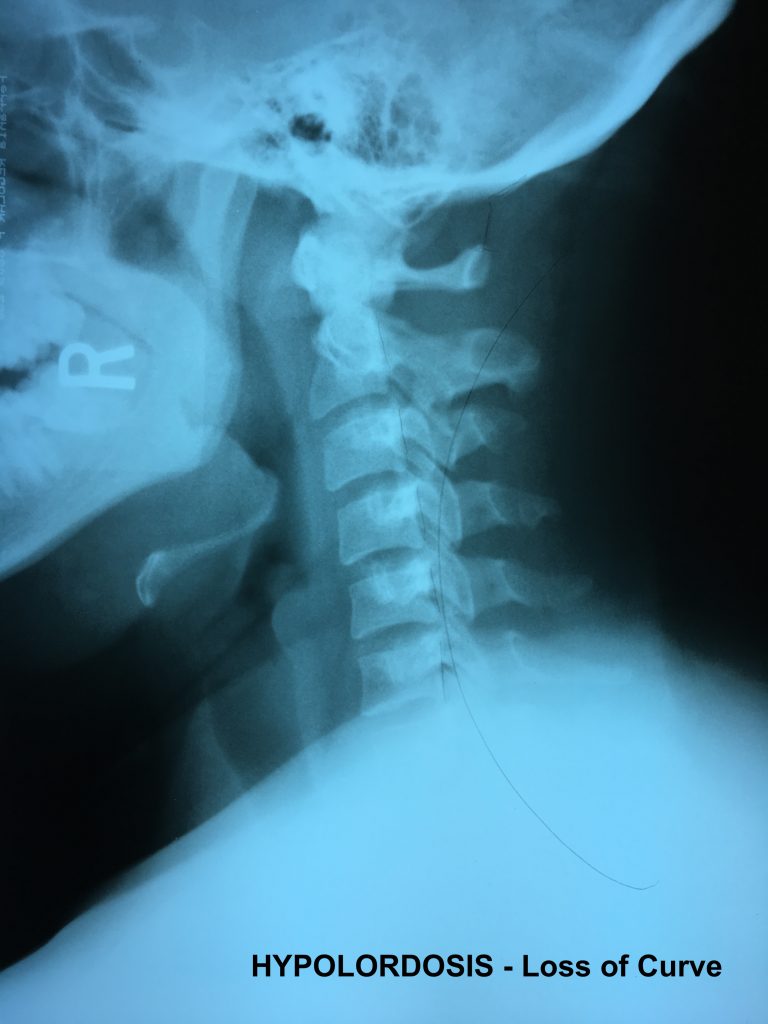

Normal vs. Abnormal Cervical XRay Chiropractic BioPhysics

Normal vs. Abnormal Cervical XRay Chiropractic BioPhysics Normal Neck X Ray Vs Whiplash so to summarize the question, yes there is a difference between whiplash and mechanical neck pain and we do treat. In the absence of clinical. Imaging plays an important role in evaluating patients with chronic neck pain. key points about whiplash. whiplash describes the manner in which a head is moved suddenly to produce a sprain in. Normal Neck X Ray Vs Whiplash.